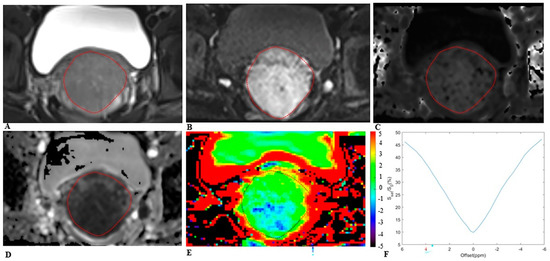

- Li, S.; He, K.; Yuan, G.; Yong, X.; Meng, X.; Feng, C.; Zhang, Y.; Kamel, I.R.; Li, Z. WHO/ISUP grade and pathological T stage of clear cell renal cell carcinoma: Value of ZOOMit diffusion kurtosis imaging and chemical exchange saturation transfer imaging. Eur. Radiol. 2022. [Google Scholar] [CrossRef]

- Hou, M.; Song, K.; Ren, J.; Wang, K.; Guo, J.; Niu, Y.; Li, Z.; Han, D. Comparative analysis of the value of amide proton transfer-weighted imaging and diffusion kurtosis imaging in evaluating the histological grade of cervical squamous carcinoma. BMC Cancer 2022, 22, 87. [Google Scholar] [CrossRef]

- Meng, N.; Wang, X.; Sun, J.; Han, D.; Ma, X.; Wang, K.; Wang, M. Application of the amide proton transfer-weighted imaging and diffusion kurtosis imaging in the study of cervical cancer. Eur. Radiol. 2020, 30, 5758–5767. [Google Scholar] [CrossRef]